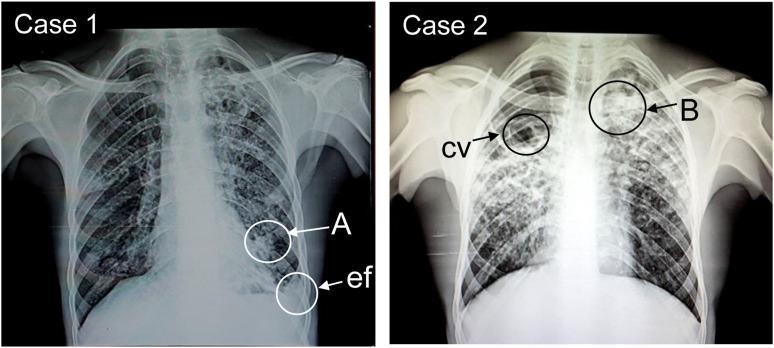

Rapidly progressive silicosis previously diagnosed as pulmonary TB in mineworkers.